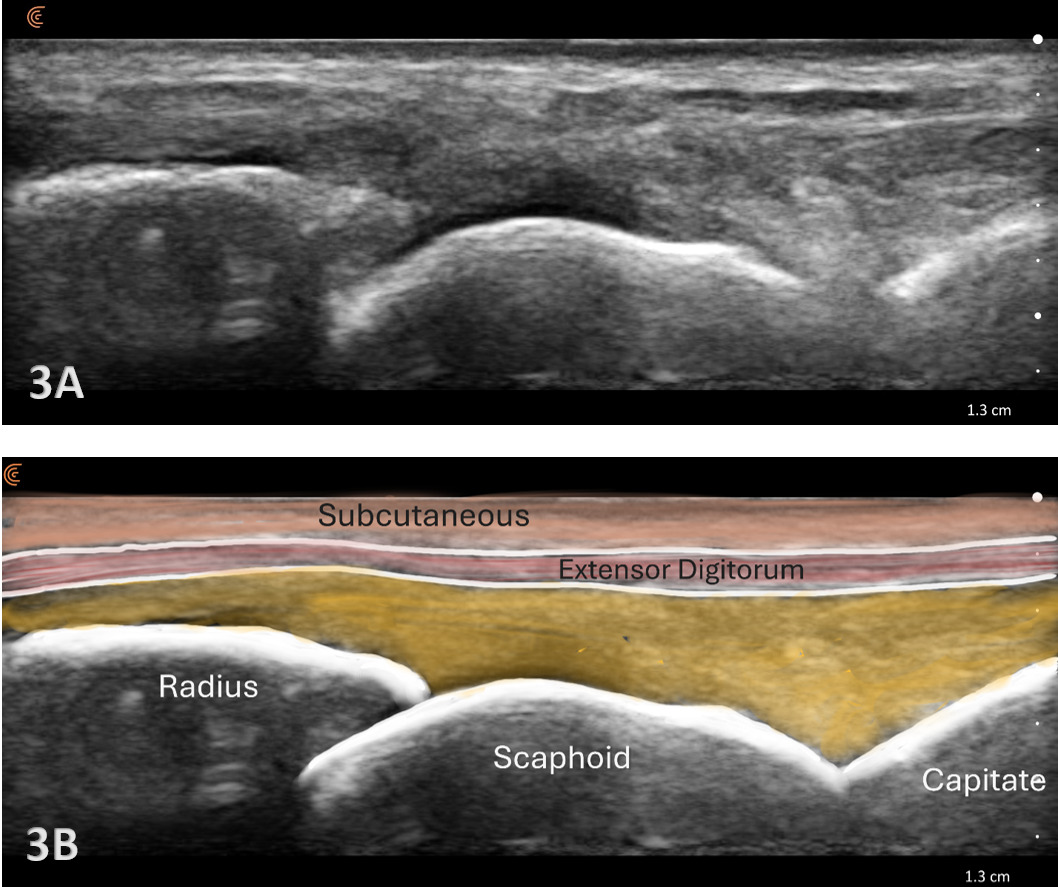

Patient Position: The patient is typically sitting with the volar forearm on the surface with the dorsal wrist facing superior. The dorsal surface is normally viewed as the structures are more superficial and easier to visualize. The transducer is placed in long axis (LAX) to view the radiocarpal joint, while, short axis (SAX) is used to view the scapholunate ligament.

Normal Sonographic Appearance

Typically, the radiocarpal joint is viewed in both the LAX and SAX. Typically, there is no joint effusion; therefore, the joint recess is collapsed or barely visible on ultrasound. The capsule should be thin and not distended. The dorsal ligaments are normally continuous and should exhibit a normal fibrillar pattern, indicating they are intact and healthy. The synovium is typically visualized as a very thin echogenic line, with no synovial hypertrophy. The articular surfaces of the radius and the carpal bones should include uniform anechoic or hypoechoic cartilage layers and demonstrate smooth, continuous hyperechoic cortical lines with no physical breaks or breaches.